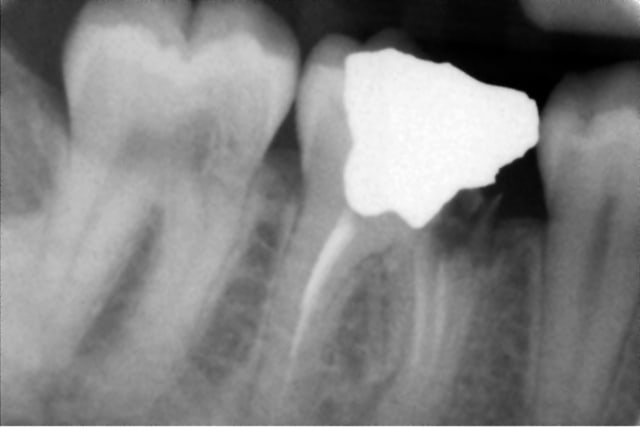

Une patiente se présente avec un abcès paro en vestibulaire de 47, elle prend des antibios depuis 5 jours. Pour le reste tout va bien et elle a une hygiène correcte.

Voilà les radios, dont une trouvée dans son dossier, qui date de 3-4 ans.

Sous la gencive, il y a un petit trou au collet de la dent, en vestibulaire. Mais la sonde s'enfonce et c'est douloureux.

IL y a une résorption peut être externe au niveau cervical mésial, et une pulpite chronique qui provoque une ostéite condensante apicale sur la racine distale. Ca fait beaucoup pour pouvoir conserver cette dent dans de bonnes conditions.